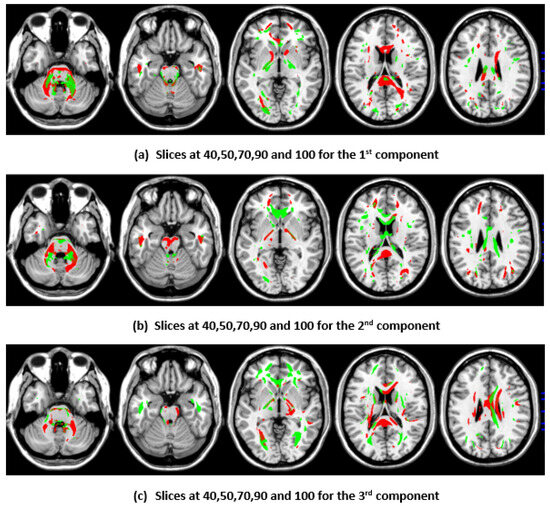

3.4. Top Brain Regions Contributing to CCA and DCCAE Components

To illustrate the brain regions, the top PCs of the first three significantly correlated GM and FA components were plotted for both the CCA results and the DCCAE results. To plot the brain regions, the CCA/DCCAE components were traced back to PCA components using the weight matrix of CCA/DCCAE, and the top PCA components were then mapped to the brain regions.

Similarly, the FA regions identified via the first component of the CCA include the corticospinal tract (7.2 cc), anterior thalamic radiation (8.4 cc), and forceps minor (3.4 cc). The second component highlights the corticospinal tract (6.3 cc), anterior thalamic radiation (8.9 cc), forceps minor (9.8 cc), and inferior longitudinal fasciculus (1.2 cc). The third component recognizes anterior thalamic radiation (9.4 cc), the forceps minor (7.7 cc), the inferior longitudinal fasciculus (2.5 cc), and the inferior fronto-occipital fasciculus (2.7 cc). Likewise, the first component of DCCAE points out anterior thalamic radiation (13.1 cc), the forceps minor (7.9 cc), the inferior longitudinal fasciculus (3.4 cc), the corticospinal tract (13.0 cc), and the inferior fronto-occipital fasciculus (2.2 cc). The second component reveals the forceps minor (12.5 cc), the inferior longitudinal fasciculus (2.0 cc), the corticospinal tract (7.9 cc), and anterior thalamic radiation (12.7 cc). The third component includes the corticospinal tract (9,4 cc), anterior thalamic radiation (10.4 cc), and the forceps minor (11.0 cc).

When examining the direct similarity between components of CCA and DCCAE, we found that most of the CCA components (for both GM and FA) have high and significant correlations (shown in Table 3 and Table 4) with some of the DCCAE components. For example, CCA GM component first is significantly and negatively correlated to DCCAE GM components first and second, and it is positively correlated to DCCAE GM component third. Similar results were observed for FA components; CCA FA component first was linked to DCCAE FA components first and second negatively and component third positively. The negative correlation observed in Table 3 and Table 4 does not indicate a fundamental contradiction in the relationship between GM and FA features. Instead, it suggests that, for the same brain region, CCA encodes a change in one direction (an increase or a decrease), while DCCAE encodes it in the opposite direction. However, the underlying GM-FA association remains consistent across both models. This difference in sign can be further illustrated in Figure 1 and Figure 3, where the first components from CCA and DCCAE show similar spatial patterns, particularly in the posterior occipital region, but the color representation differs, indicating an increase in one model and a decrease in the other.

Figure 2. First, second, and third components of FA identified through CCA.